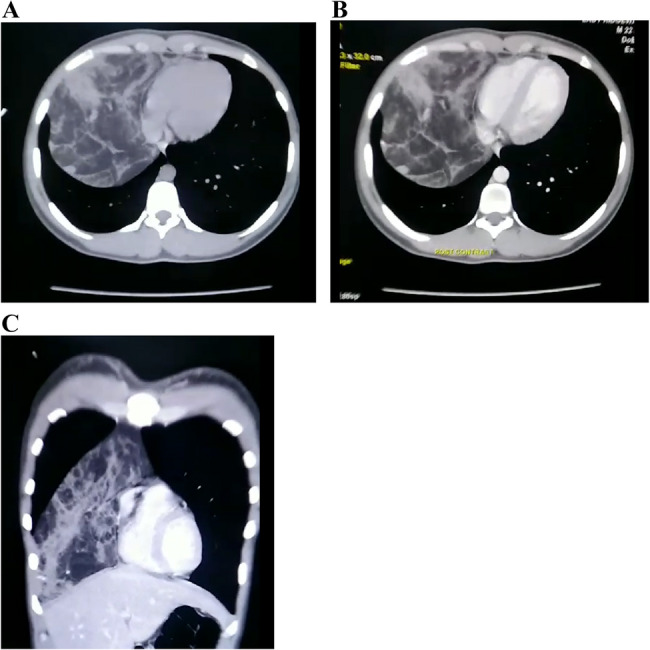

Case presentation: A 22-year-old university student was incidentally noted to have abnormal findings on cardiorespiratory examination. A chest X-ray suggested dextrocardia with cardiomegaly, but further imaging revealed a large anterior mediastinal mass. Contrast-enhanced computed tomography (CT) of the chest showed a well-encapsulated, predominantly fat-density mass (approximately 24 × 15 × 12 cm) in the anterior mediastinum extending into the right hemithorax without invasion of adjacent structures. The lesion caused rightward mediastinal widening but no actual cardiac enlargement, dextroposition or lung collapse. Surgical resection via right mini-thoracotomy was performed. The Gross examination revealed a large, lobulated, encapsulated tumour with a yellow, fatty cut surface and interspersed solid areas. Histopathology confirmed the presence of mature adipose tissue with thymic lobules (cortex, medulla, and Hassall's corpuscles), consistent with thymolipoma, showing no evidence of malignancy. The patient's postoperative recovery was uneventful, and the heart resumed its normal anatomical position.